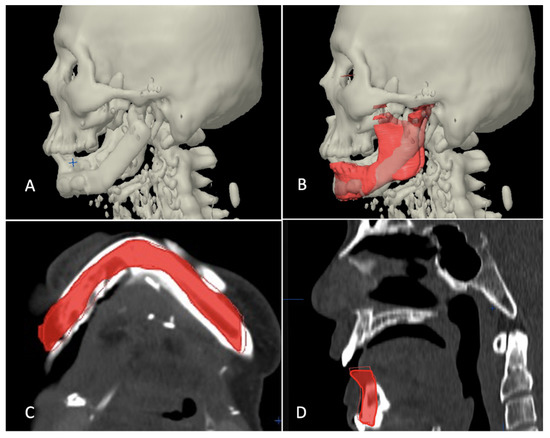

Figure 9.

Superimposition of planned and postoperative image in category II. (A) 3-dimensional view of outcome after reconstruction. (B) Superimposition of virtual plan (purple color) and post-operative data. (C,D) Axial view showing good match of reconstructed fibula to simulated mandible.